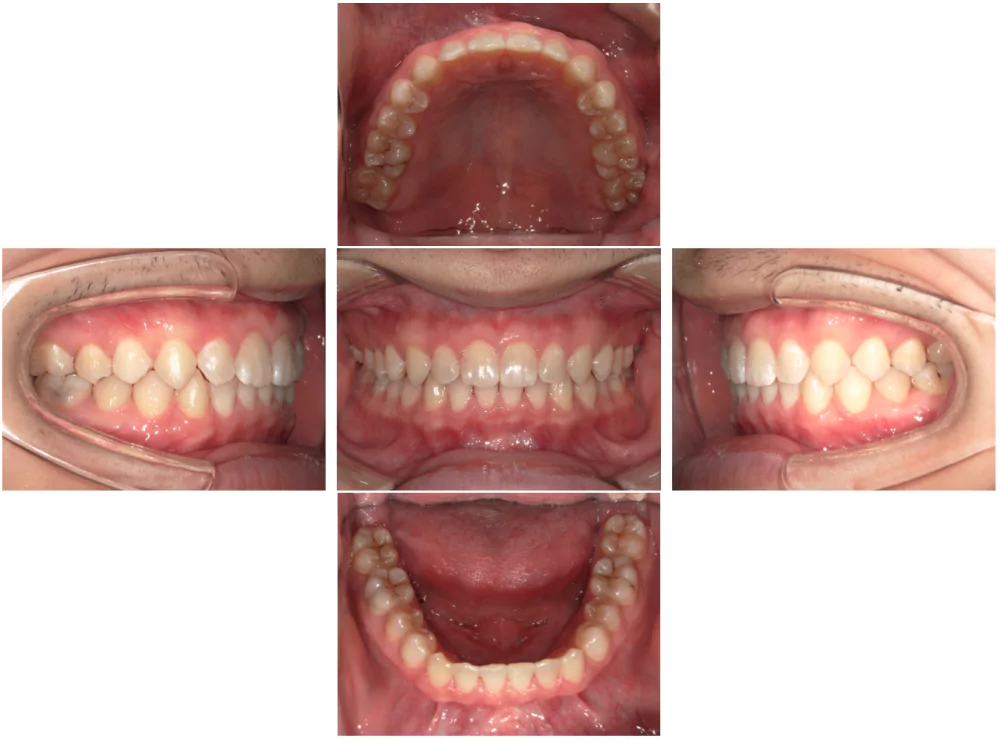

症例3

| 来院時の主訴 | 歯の間の隙間を閉じたい |

| 医院での対応や適用装置 | マウスピース矯正装置を使用して主訴である歯の間の隙間を閉じて改善を行いました。 歯の隙間の原因は飲み込み時に舌を前に出してしまう癖だと考えられましたので、 トレーニングを行い癖も無くなりました。 |

| 通院期間 | 6ヶ月 |

| 通院回数 | 5回 |

| 治療費用総額 | 577,500円(税込) |

| リスクと副作用 | 矯正治療による歯の移動に伴う痛み、歯根吸収、虫歯 |